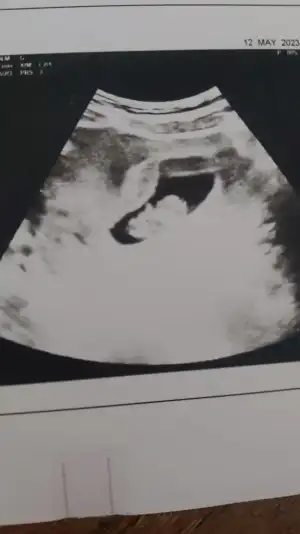

sata göre 10+1 ama ultrasonda 11+0 çıktık. NİPT için kan verdim. hayırlı sonuçlar olur inşaallah.

Siz ne hissediyosnuz cinsiyet fotolar ekledim :)

sata göre 10+1 ama ultrasonda 11+0 çıktık. NİPT için kan verdim. hayırlı sonuçlar olur inşaallah.

Siz ne hissediyosnuz cinsiyet fotolar ekledim :)